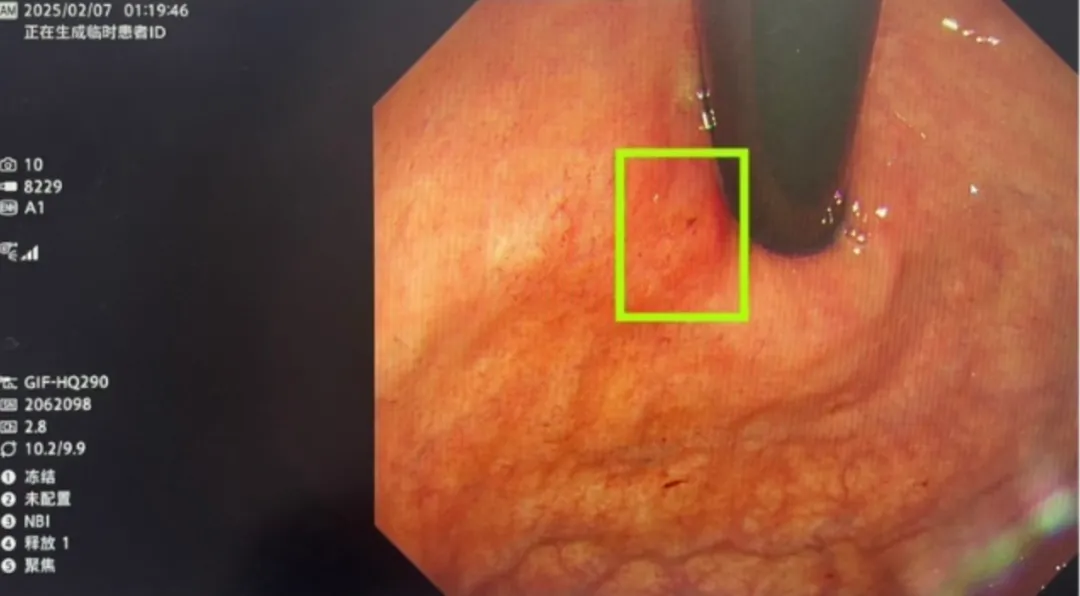

6.1.术前筛查AI辅助内镜检查不仅可发现肉眼遗漏病灶、显著提高早期癌症筛出率,还能够协助操作者判断病变浸润深度、侵及范围

6.5.“内镜帧探”帮医生睁开“第三只眼”精准捕捉到4mm的胃早癌